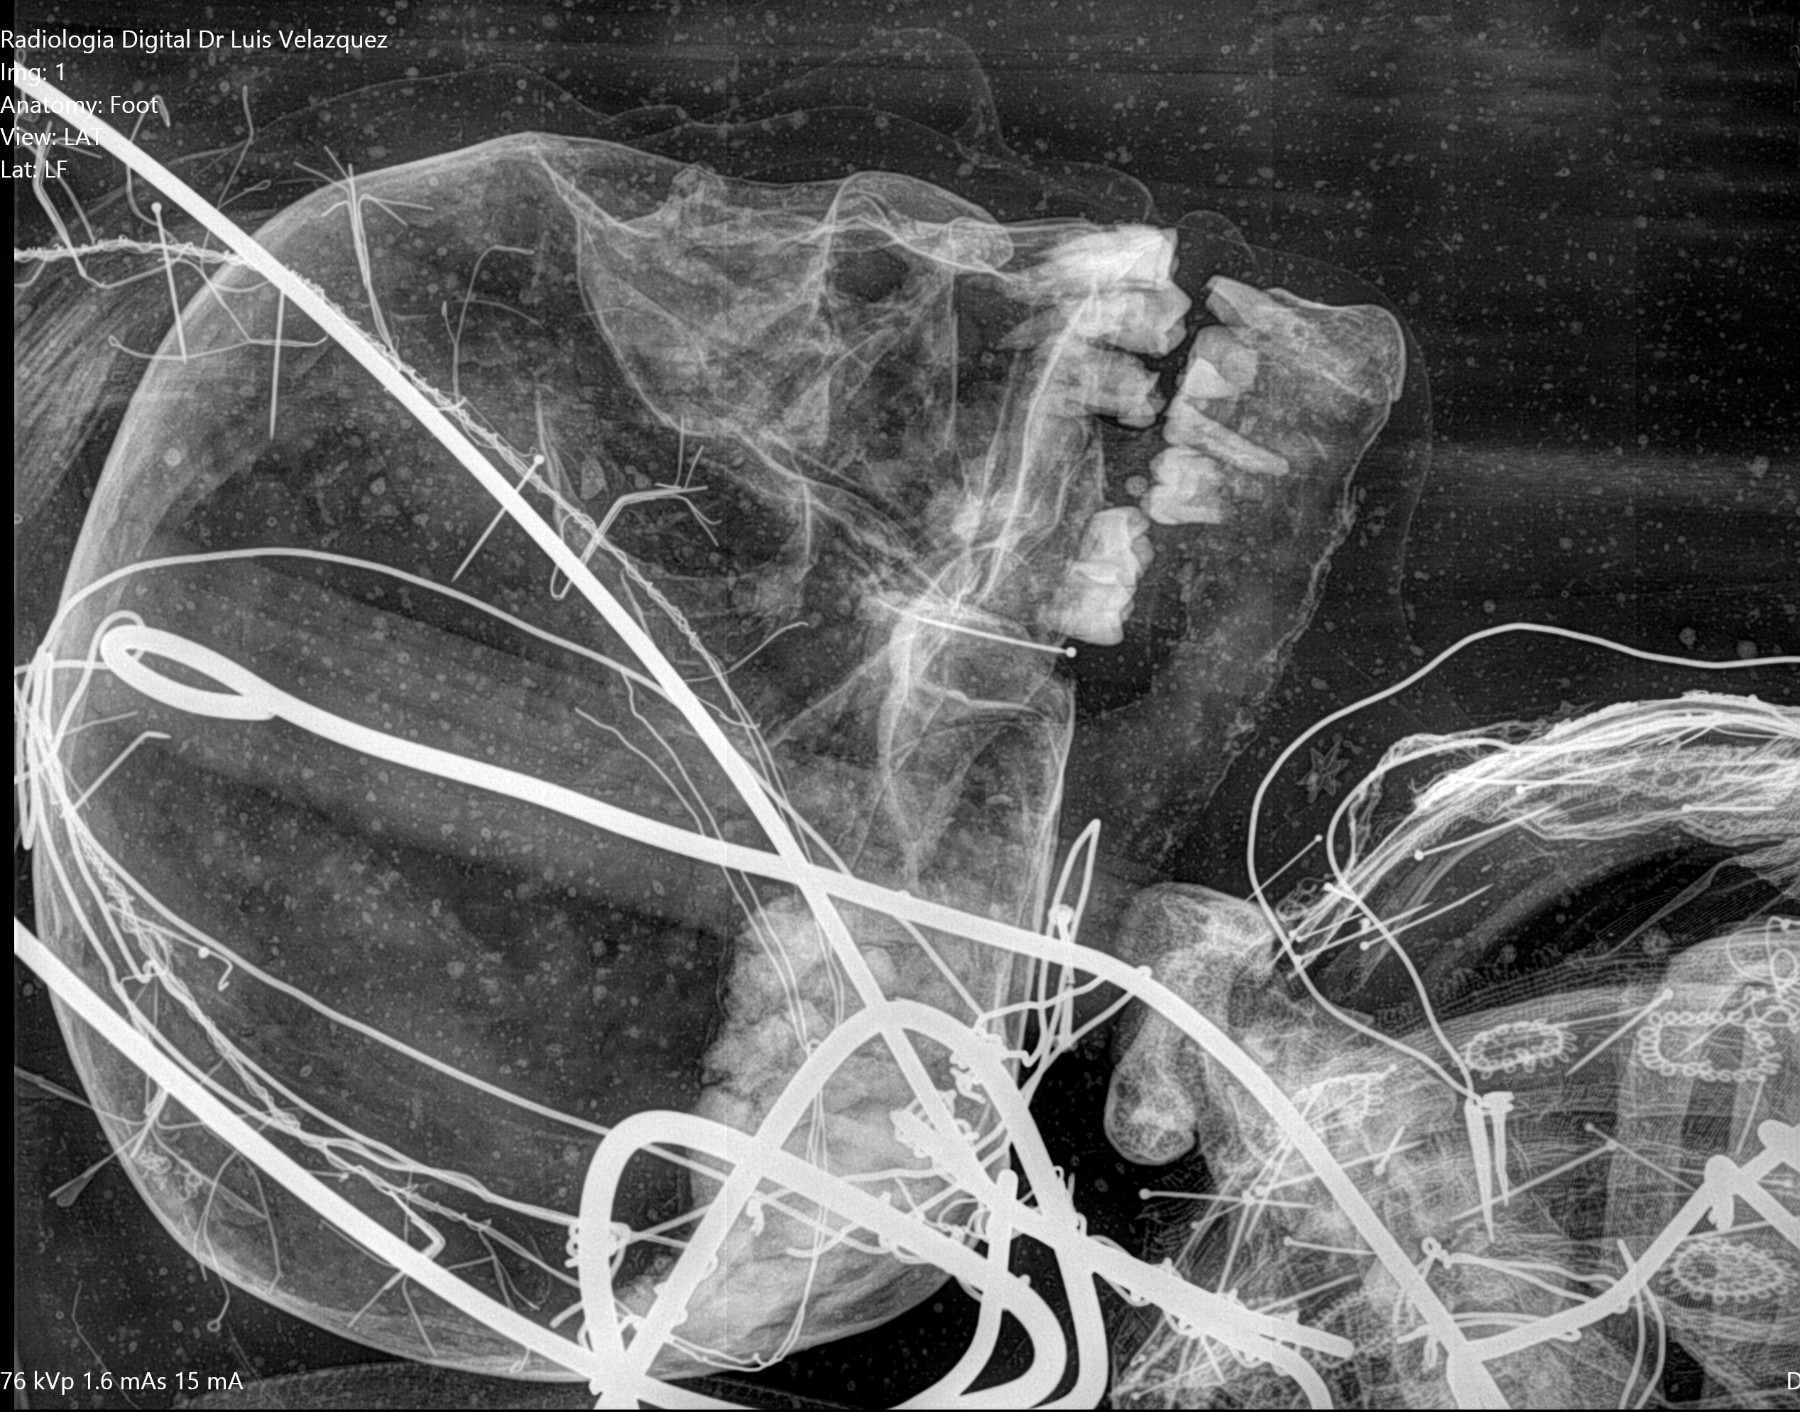

Radiología Digital como Herramienta Complementaria en el Dictamen de Bienes Muebles

Desde el descubrimiento de los rayos “X” y las placas radiográficas por Wilhelm Conrad Roentgen y su posterior difusión a través de la Asociación Físico médica de Wurzburg el 28 de diciembre de 1895, que fue la primera asociación que habló de los nuevos rayos que podían penetrar el cuerpo y fotografiar los huesos, ha habido muchos cambios tanto en la forma de obtener, procesar e incluso en la forma de visualizar, manejar y almacenar las placas radiográficas.